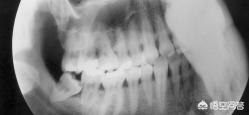

1、閉塞歯、特に十代と二十代の若者は、頭痛を繰り返すと、このような歯のフィルムを取ることができ、最後の歯が水平に成長し、これは非常に炎症を再発しやすく、重度の歯痛や頭痛を引き起こします。これは、ブロックされた歯を除去し、口腔衛生に注意を払うことによって治すことができる。